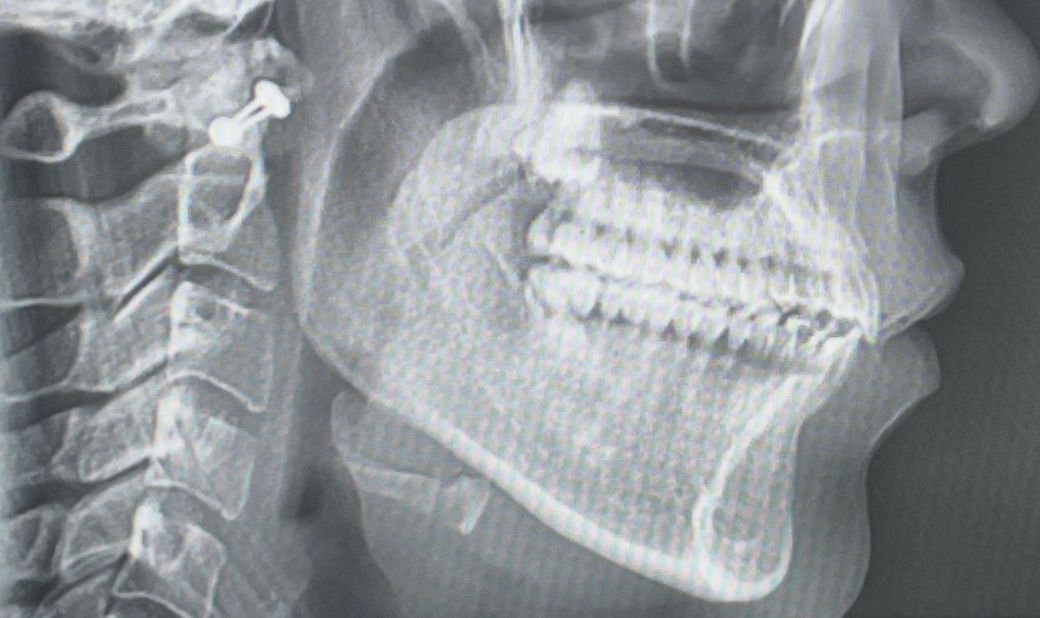

사진은 순서대로 턱 뒤로 회전하기 전,후입니다.

현재 엑스레이 사진상으론 어금니 교합은 정상적입니다. 치아 교합보다는 턱관절 문제에 집중해봐야 할 것 같습니다